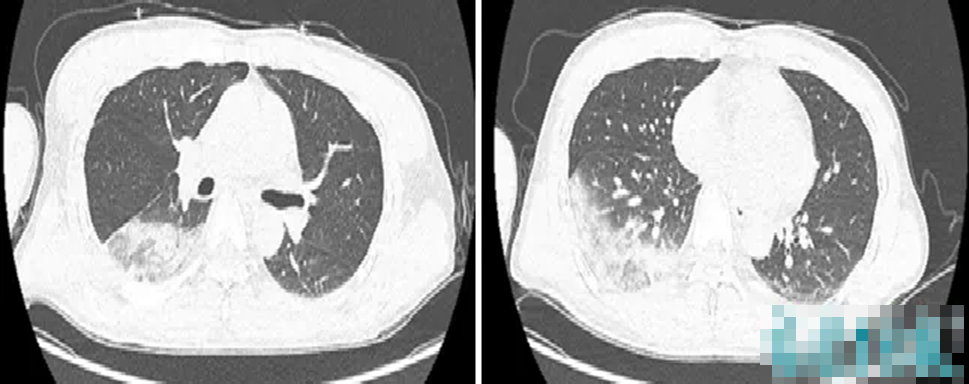

Kết quả kiểm tra cho thấy hai thuỳ phổi dưới đã viêm, chức năng gan thận đều tổn thương, chỉ số viêm tăng cao bất thường.